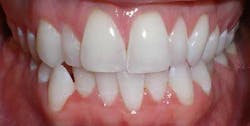

A 27-year-old female presented with a chief complaint of crowding on the upper and lower arches. Upon evaluation, it was noted that the patient had 2 mm and 4.5 mm of maxillary and mandibular arch length deficiency respectively, a missing lower left second bicuspid with primary tooth still present, small upper lateral incisors, cross-bite of the lower right canine, and lower midline shift to the right of 2 mm. (Figs. 1-8)

Figs. 1-8